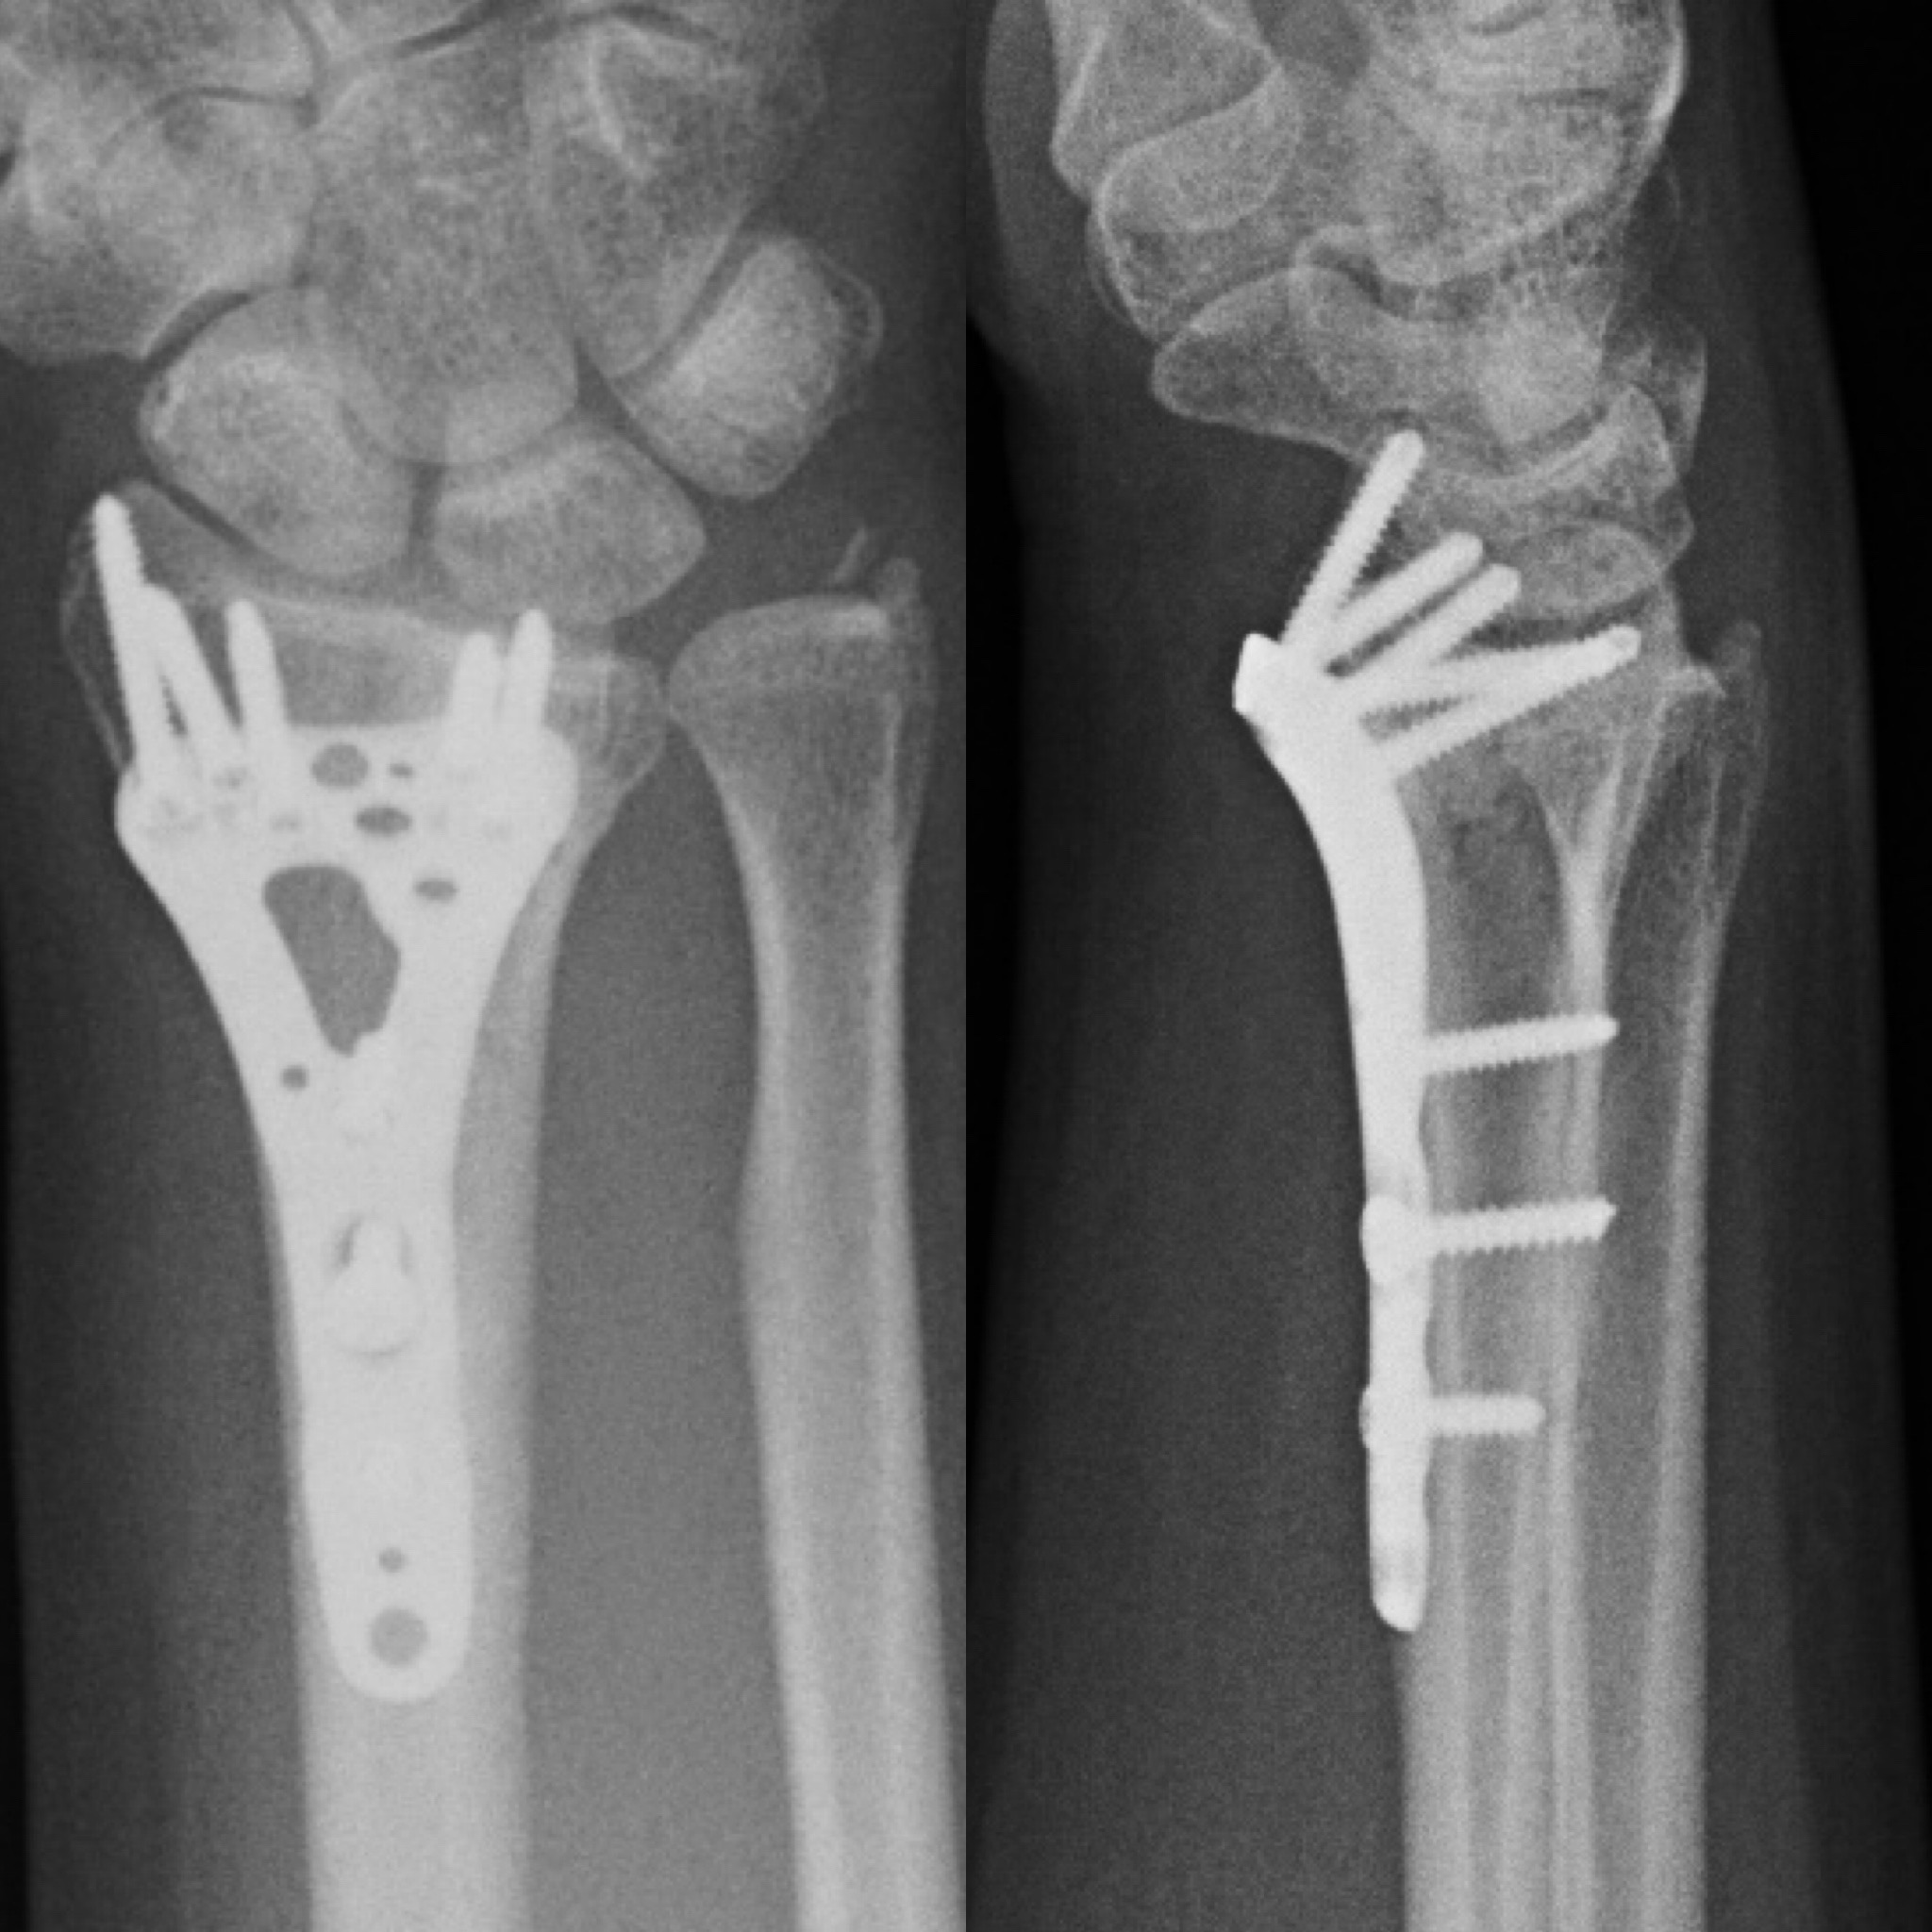

Клинический случай: внутрисуставной перелом дистального метаэпифиза лучевой кости — после операции

Контрольный осмотр и ранний послеоперационный результат.